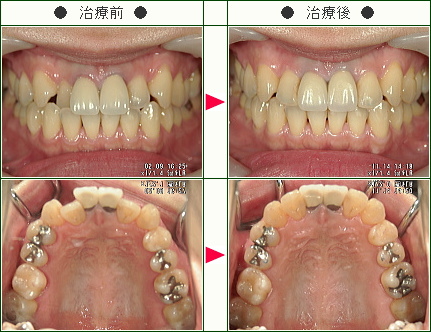

☆歯のデコボコ矯正症例(M.K.様 35歳 女性)